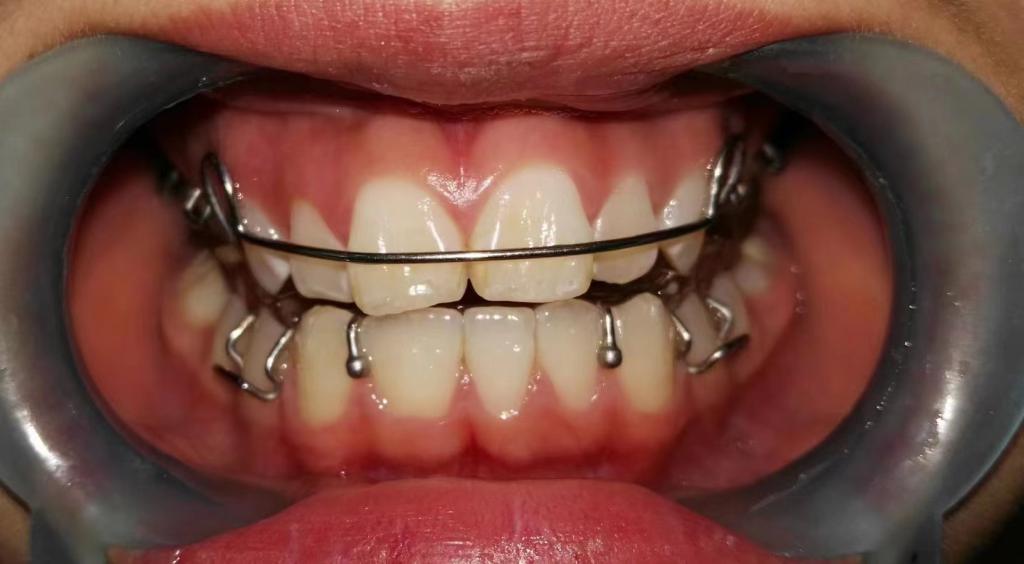

② 前方牵引矫治器

矫治方法:前牙反合的患儿往往伴有咬上唇、伸下巴、口呼吸等不良习惯。因此,应首先纠正其不良习惯。口呼吸习惯应进行耳鼻喉科会诊处理,检查其是否伴有鼻咽部疾病,排除鼻咽部疾病后,再进行纠正。对于乳牙列,常用的矫治器为合垫舌簧矫治器;对于混合牙列,常用的矫治器为前方牵引矫治器和FRⅢ矫治器。